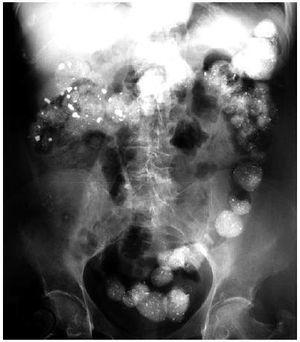

Mujer de 62 años en hemodiálsis crónica desde hace 6 años, con Diabetes Mellitus, hiperparatiroidismo secundario e hipertensión arterial como antecedentes personales más importantes. Consulta por sensación de plenitud abdominal, estreñimiento y nauseas. La exploración física y resultados analíticos fueron irrelevantes, destacando en la radiografía simple de abdomen material radio-opaco, disperso por todo el recorrido del colon, recordando una imagen de cielo estrellado. Revisando el tratamiento, se observó que desde hacía cuatro meses estaba tomando Carbonato de Lantano. Inicialmente asociado a otros quelantes del fósforo. La paciente no había recibido ningún tipo de contraste en los últimos 6 meses. Tras la retirada del Carbonato de Lantano y tratamiento con laxantes, la sintomatología desapareció y en la radiografía de abdomen realizada 3 semanas después apenas se apreciaba material radio-opaco.

Figura 1. Radiografía de abdomen en vacío inicial